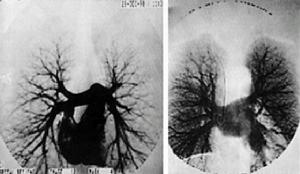

糖尿病大血管病變主要是大中血管動脈粥樣硬化引起的。發生病變的血管壁有粥樣硬化斑塊形成,斑塊中有脂質如膽固醇等沉積,使血管腔狹窄、堵塞。由於動脈血管中循環著攜帶有氧氣的血液,若供應某一器官組織的血管腔狹窄,則該器官組織發生缺血、壞死。如果發生在供應心臟的冠狀動脈、則導致心肌缺血甚至心肌梗塞;如果腦血管動脈粥硬化,則會發生腦梗塞,以多發性腔隙性腦梗死多見;如果在下肢動脈,會出現下肢疼痛、間歇性跛行甚至下肢潰瘍、壞死。

包括冠狀動脈硬化,腦動脈硬化,腎動脈硬化及下肢動脈硬化,由於血脂高、血糖高、血液沾度高,極易發生粥樣硬化,是糖尿病病人患冠心病發生和發展的主要危險因素之一。冠心病主要表現為心絞痛、心肌梗塞、心力衰竭和心律失常。糖尿病病人的高血壓發病率為35%-40%,較不是糖尿病的人高出5-10倍,伴高血壓者常有頭暈、頭痛、煩燥易怒、失眠、多熱等表現。